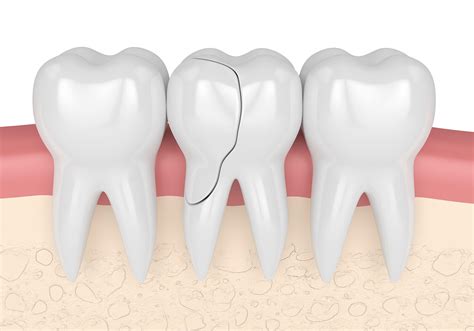

Not all cracks are created equal. In dentistry, cracking in teeth is categorized based on depth, location, and the severity of the damage. Most adults eventually develop “craze lines”—tiny, superficial cracks that only affect the outer enamel. These are generally harmless and do not require treatment. However, more significant fractures can extend into the dentin (the layer beneath the enamel) or even down into the pulp, which contains the tooth’s nerves and blood vessels.

When a fracture progresses, it changes how your tooth interacts with temperature, pressure, and biting forces. Identifying the type of crack early is the most effective way to prevent the loss of the tooth structure.